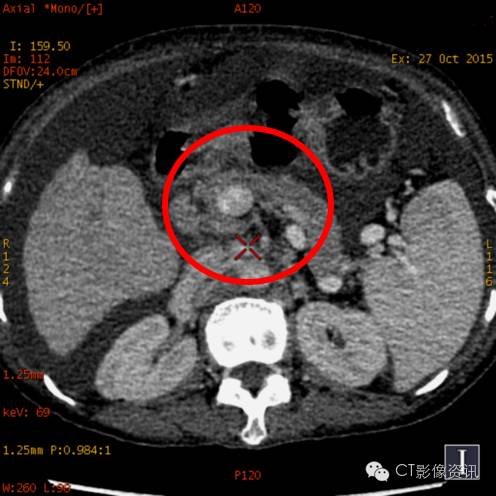

CT诊断

小结 肝脏具有肝动脉和门静脉双重血供特点,肝硬化时由于门脉压力升高,导致门脉血供减少,为保证肝脏的营养肝动脉供血相对增加即肝动脉缓冲效应(Hepatic Arterial Buffer Response,HABR),以致肝脏的双重血供比例失调。 能谱CT可以实现物质分离功能,能够直接测量肝脏增强扫描各期肝实质的碘含量,并可计算出肝动脉碘分数(Arterial Iodine Fraction,AIF)与门静脉碘含量(PortalVenous Iodine Concentration,PVIC)。本例通过肝脏病变血供情况的定量分析,提供更多诊断信息。